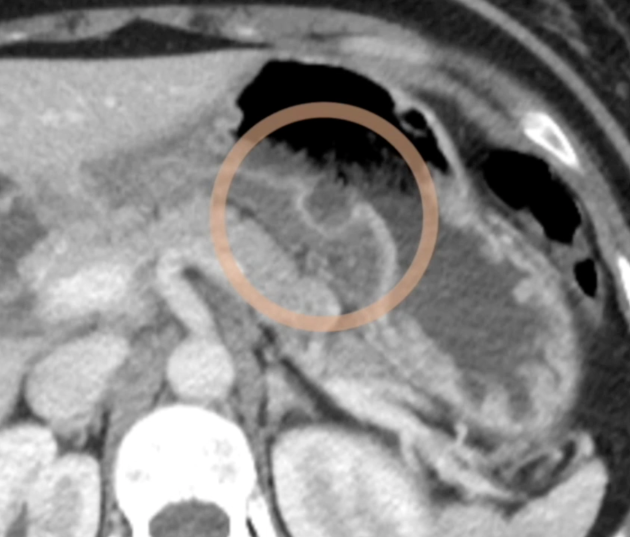

- Cratères

- Oedème sous-muqueux

- Infiltration du ligament Gastro-Hépatique

- Epaississement de la paroi gastrique